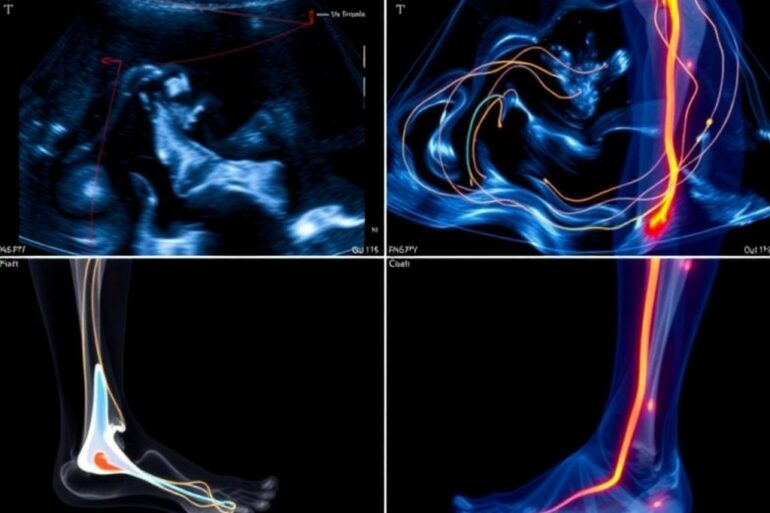

Ультразвуковое исследование вен ног — это тот простой и информативный тест, к которому стоит обратиться, если нога внезапно заболела, припухла...

Ультразвуковое исследование давно стало одним из самых востребованных методов диагностики. Его назначают при плановых осмотрах, при появлении тревожных симптомов и...